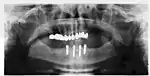

Success or failure of implants depends primarily on the thickness and health of the bone and gingival tissues that surround the implant, but also on the health of the person receiving the treatment and drugs which affect the chances of osseointegration. The amount of stress that will be put on the implant and fixture during normal function is also evaluated. Planning the position and number of implants is key to the long-term health of the prosthetic since biomechanical forces created during chewing can be significant. The position of implants is determined by the position and angle of adjacent teeth, by lab simulations or by using computed tomography with CAD/CAM simulations and surgical guides called stents. The prerequisites for long-term success of osseointegrated dental implants are healthy bone and gingiva. Since both can atrophy after tooth extraction, pre-prosthetic procedures such as sinus lifts or gingival grafts are sometimes required to recreate ideal bone and gingiva.

When a more exacting plan is needed beyond clinical judgment, the dentist will make an acrylic guide (called a stent) prior to surgery which guides optimal positioning of the implant. Increasingly, dentists opt to get a CT scan of the jaws and any existing dentures, then plan the surgery on CAD/CAM software. The stent can then be made using stereolithography following computerized planning of a case from the CT scan. The use of CT scanning in complex cases also helps the surgeon identify and avoid vital structures such as the inferior alveolar nerve and the sinus.[31][32]: 1199